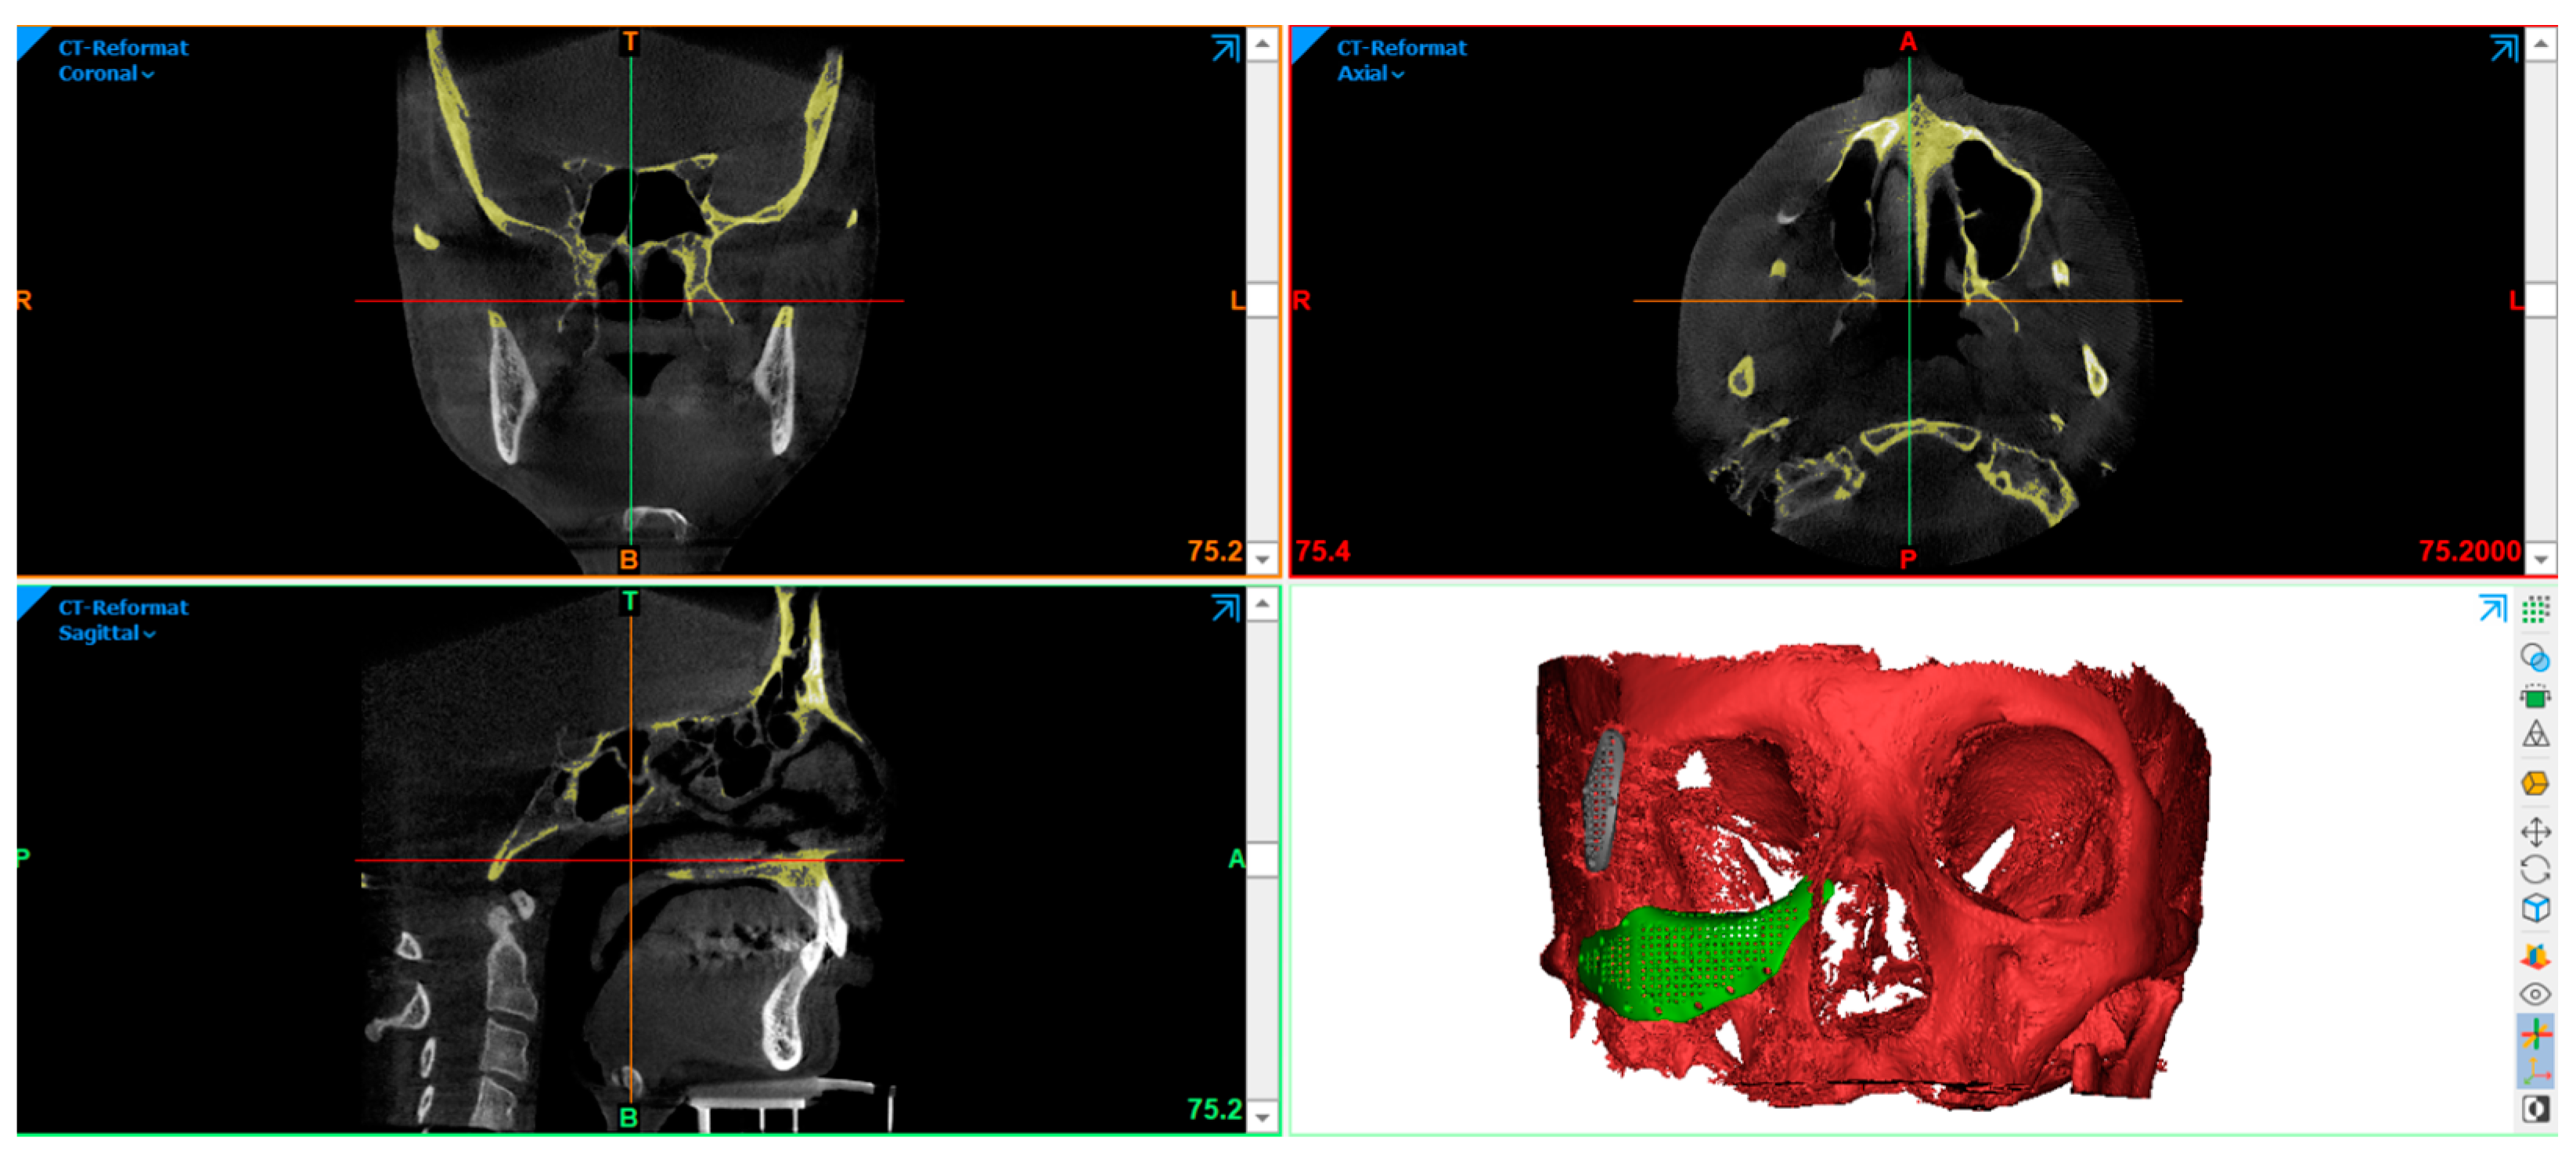

2.2. Skull Model Generation

2.3. PSI Design

2.4. Virtual Planning of Patients-Specific Implants